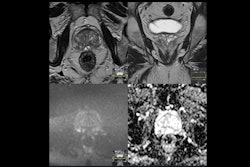

Of the 68 medical centers the study team sent the survey to, 44 submitted only their compliance with PI-RADSv2.1 technical recommendations, while 26 completed the full survey. Thirteen hospitals provided 252 usable images from anonymized prostate MRI examinations of biopsy-naive men suspected of prostate cancer. The mean compliance with PI-RADS recommendations was 79%.

The results from the survey showed that while compliance with PI-RADS recommendations was high, 30% to 50% of the prostate MRI examinations were of inadequate image quality.

Among the factors potentially associated with image quality, specialized education for the radiologist was significant. The findings showed that images from hospitals where radiologists had taken a dedicated course on reporting prostate MRI received higher quality scores, in particular on T2-weighted (T2W) signal-to-noise ratio (SNR), total T2W quality, and total biparametric quality.